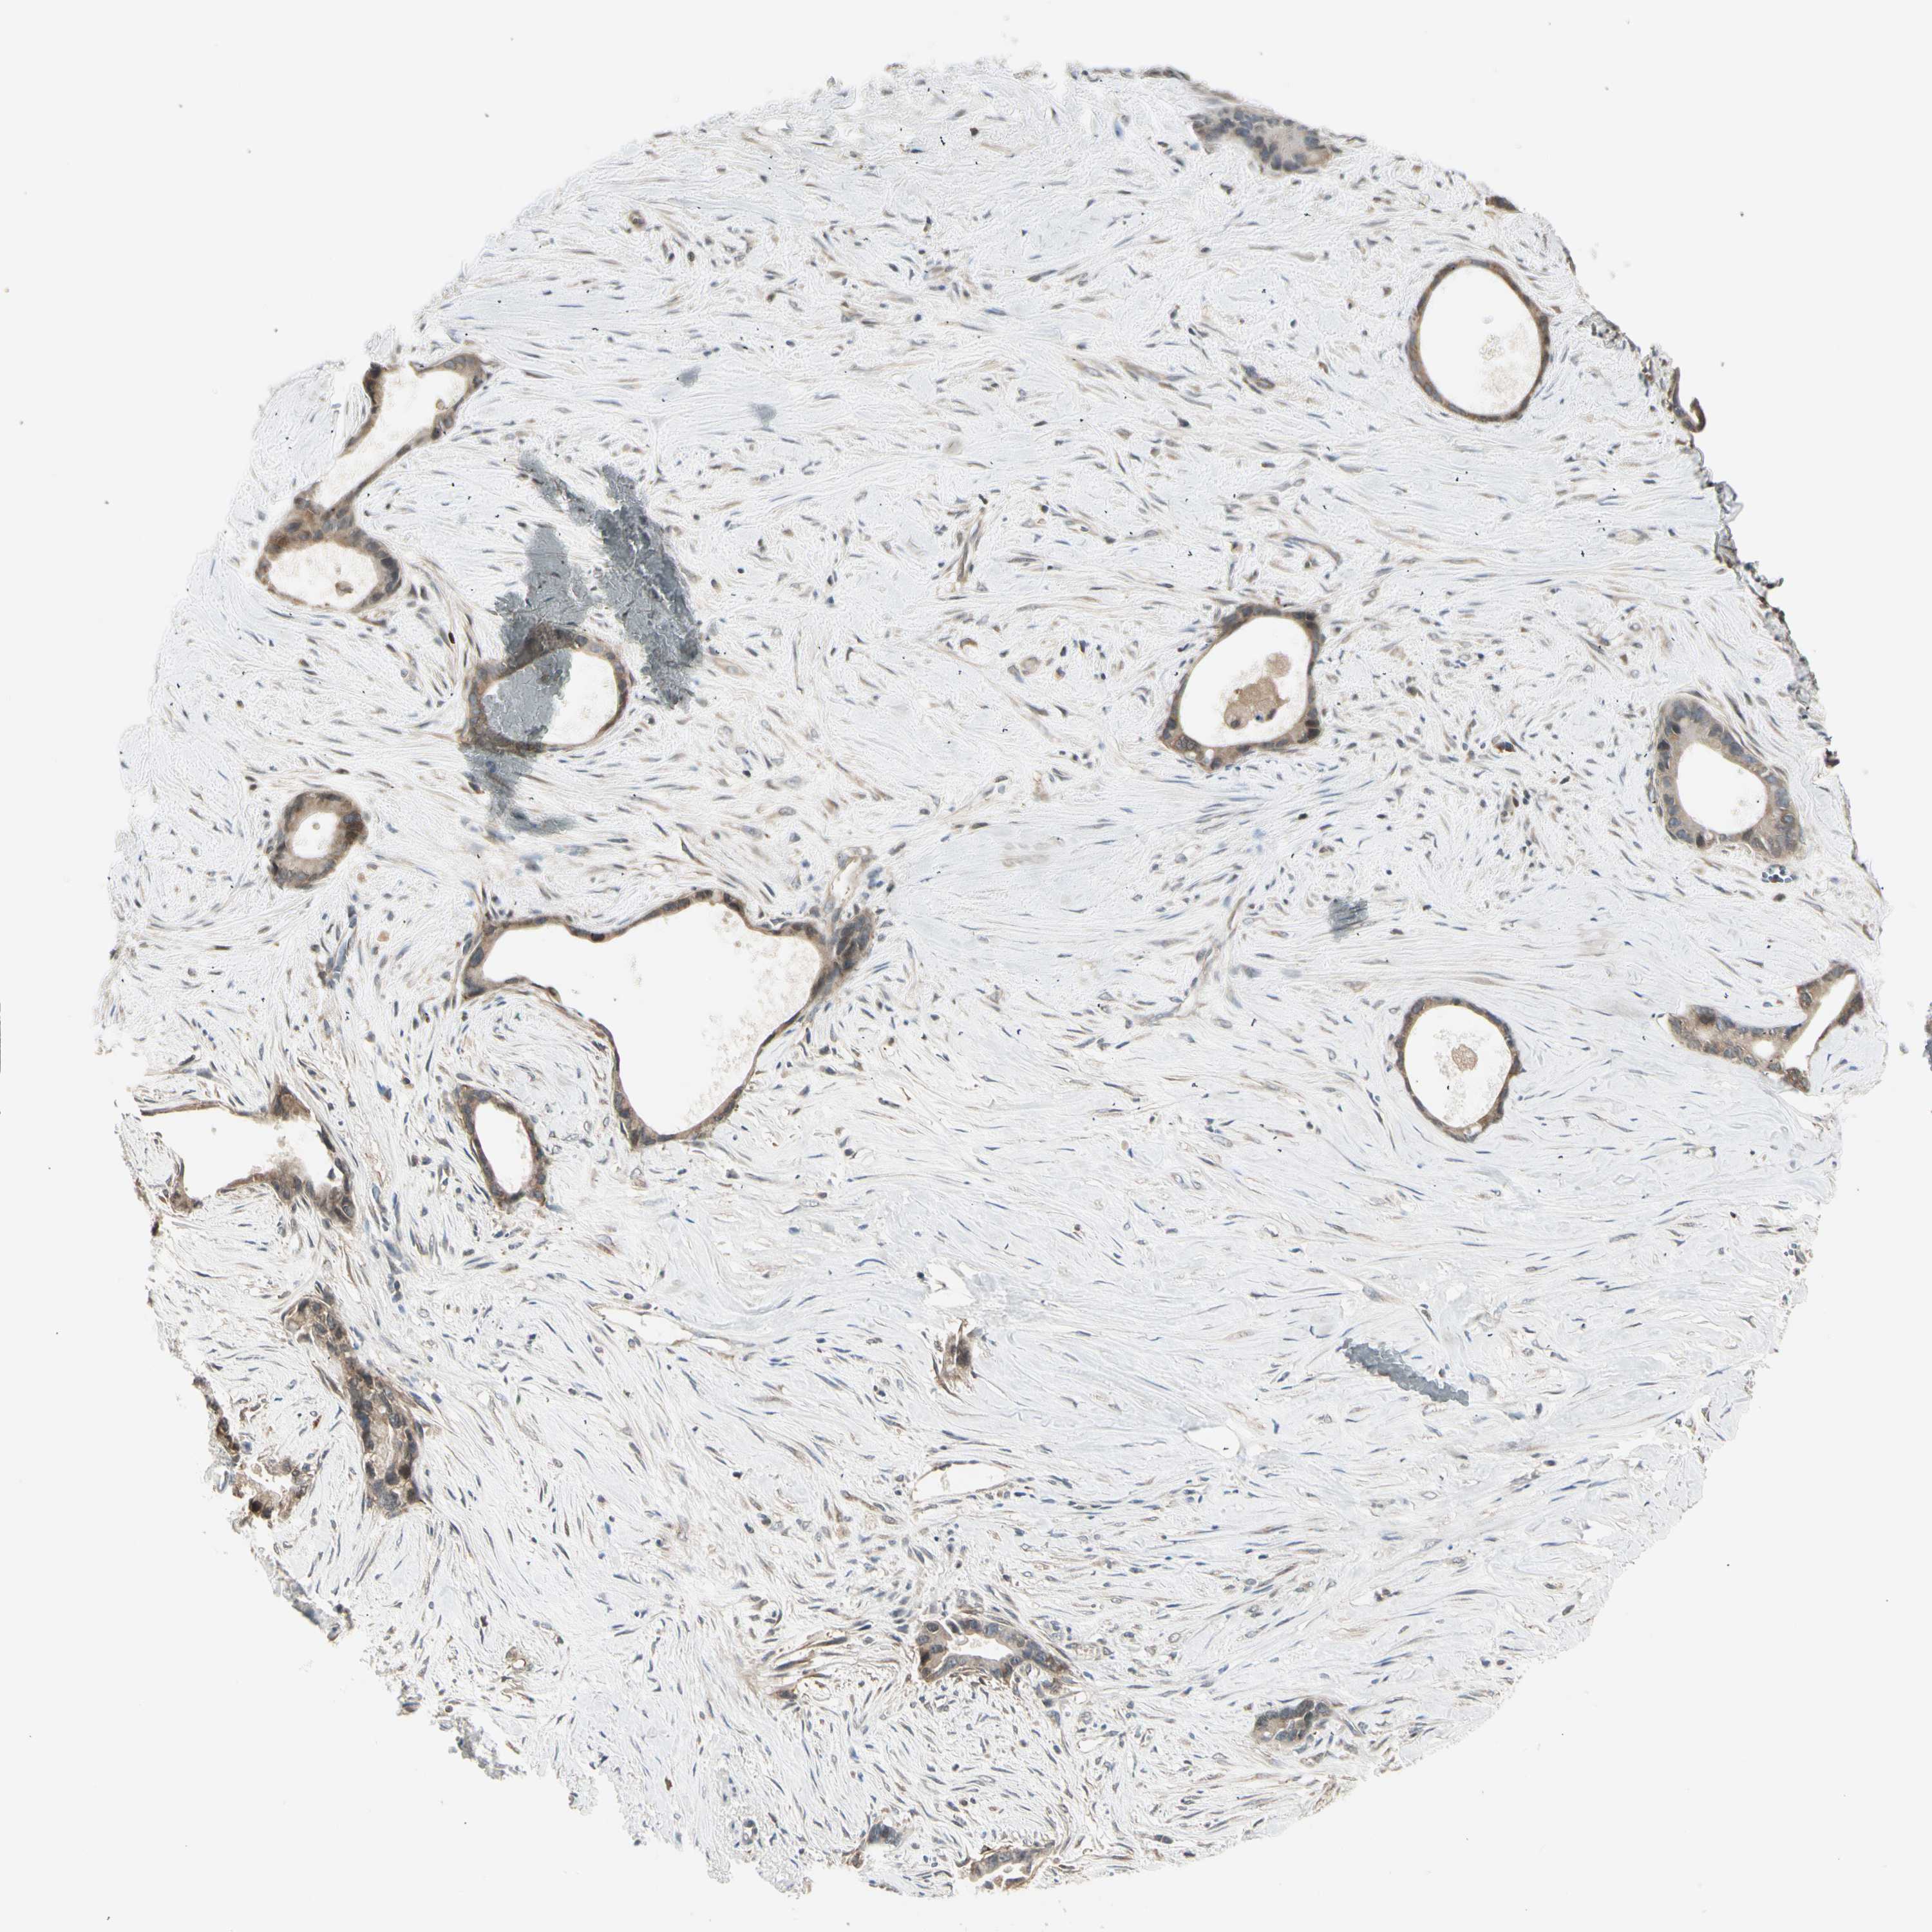

LIVER CANCER - Protein expressioni

A mouse-over function shows sample information and annotation data. Click on an image to view it in a full screen mode. Samples can be filtered based on level of antibody staining by selecting one or several of the following categories: high, medium, low and not detected. The assay and annotation is described here.

Note that samples used for immunohistochemistry by the Human Protein Atlas do not correspond to samples in the TCGA dataset.

Antibody stainingi

Antibody staining in the annotated cell types in the current human tissue is reported as not detected, low, medium, or high, based on conventional immunohistochemistry profiling in selected tissues. This score is based on the combination of the staining intensity and fraction of stained cells.

Each image is clickable and will lead to virtual microscopy that enables deeper exploration of all samples and also displays staining intensity scores, fraction scores and subcellular localization as well as patient and tissue information for each sample.

Antibody HPA008237

Antibody CAB017181

Staining

High

Medium

Low

Not detected

Intensity

Strong

Moderate

Weak

Negative

Quantity

>75%

75%-25%

<25%

None

Location

Nuclear

Cytoplasmic/membranous

Cytoplasmic/membranous,nuclear

Cholangiocarcinoma

Carcinoma, Hepatocellular, NOS